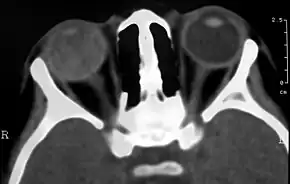

Imaging studies such as ultrasonography (US), Computerized Tomography (CT) and Magnetic Resonance Imaging (MRI) can aid diagnosis. On ultrasound, Coats' disease appears as a hyperechoic mass in the posterior vitreous without posterior acoustic shadowing; vitreous and subretinal hemorrhage may often be observed.[7][8]

On CT, the globe appears hyperdense compared to normal vitreous due to the proteinaceous exudate, which may obliterate the vitreous space in advanced disease. The anterior margin of the subretinal exudate enhances with contrast. Since the retina is fixed posteriorly at the optic disc, this enhancement has a V-shaped configuration.[3]